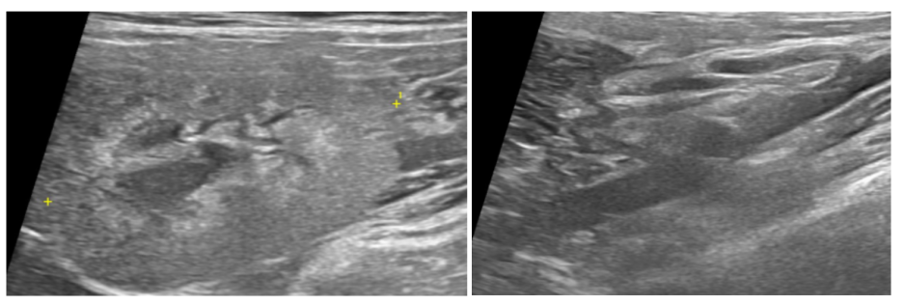

본 환자는 좌측 신장 구조물이 확인되지 않는 선천적 신장 무형성 환자입니다.

우측신장구조물(좌) / 좌측신장구조물 미확인(우) / 출처: 에스동물메디컬센터

양산 에스 고양이 초음파 – 우측신장구조물(좌) / 좌측신장구조물 미확인(우)

즉, 한쪽 신장에 의존해 살아왔으나 나이가 들면서 기능이 급격히 떨어진 상태였던 것입니다.